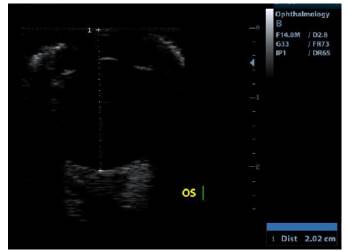

Se realizó ecografía ocular con transductor lineal de 14 MHz para evaluar extensión de la lesión, se apreció engrosamiento iridal severo en región ventrolateral del mismo con presencia de una masa adherida (no medida) con una porción hipoecoica hacia anterior y dos porciones anecoicas hacia posterior de la lesión (Figura 4), la ecogenicidad de la cámara anterior, cámara posterior y cámara vítrea se encontró conservada, la posición y ecogenicidad del lente se encontraron adecuadas, la túnica posterior estaba posicionada adecuadamente (Figura 5).